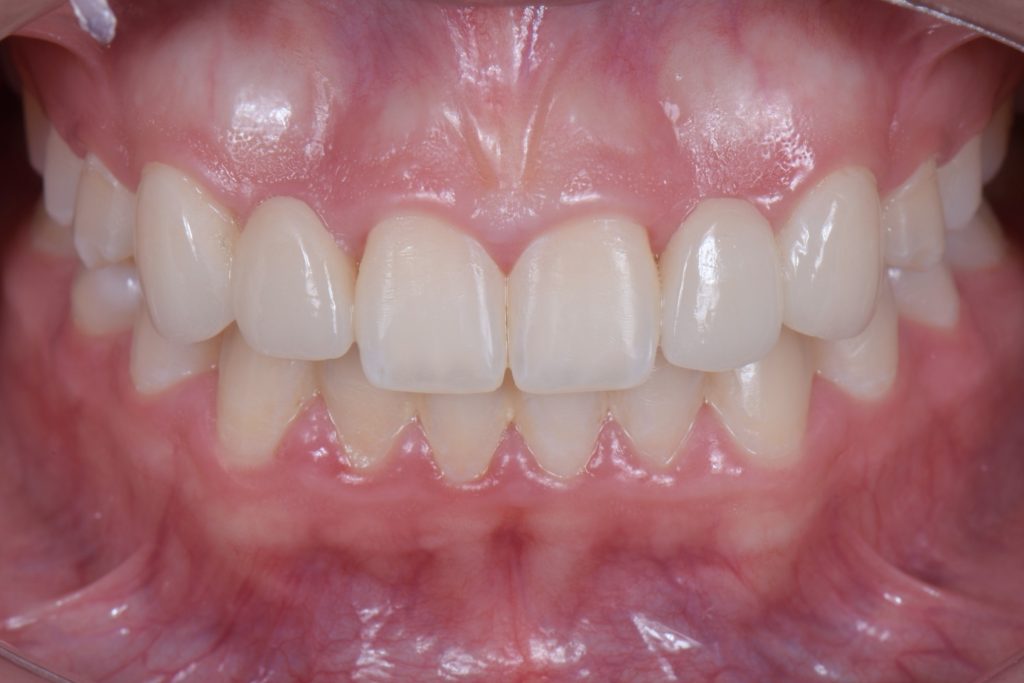

Solution #3: Cantilever Bridge

A fundamental principle in contemporary therapy is to conserve tooth structure by being as minimally invasive as possible. Today, doing a full-coverage restoration on intact natural teeth is extremely difficult to justify, but there are specific conditions where a cantilever bridge can be considered a choice solution.

In this case, a 16-year-old female (Figs. 13-23) presented with congenitally missing lateral incisors with significantly undersized canines that were out of occlusion. Both these specific features meant that from a functional and esthetic standpoint (tooth position and size), the canines required additional contour to attain a favorable occlusal contact and a more dominant contour, characteristic of a maxillary canine.

So, I needed to make sure that there was enough space for the restorative material. A purely additive wax-up was required to attain a mockup, verifying that the proposed contours were esthetically pleasing. This can be obtained either by an analogic approach (Fig. 15) or a digital approach (Fig. 16).

Incisally, there was no reduction required, the reduction was minimal, and from a cervical perspective, a 0.5 mm finish line was prepared (Fig. 17). This allowed our team to do a fundamentally additive design.

It is important here to emphasize that even if the age and preference of the patient allowed us to plan for an implant-supported restoration to replace the lateral incisors, the need to enhance the contours of the canines would still be required to provide a functional and esthetically pleasing result.

The undersized canines were out of function, removing all protective coverage for the lateral incisors. This provided a unique opportunity and indication for the most conservative scenario of a cantilevered RBFDP.

When considering a zirconia crown, we needed to ensure there was sufficient room for the wall thickness to be a minimum of 0.3 mm (ideally between 1.0 mm and 1.5 mm), an incisal reduction of 2.0 mm, and a visible and continuous circumferential chamfer with a reduction of at least 0.5 mm at the gingival margin. The patient’s preliminary condition allowed us to accomplish these space requirements with hardly any tooth reduction (Fig. 17).

RBFPD has an exceptional record, so this cantilever bridge can be considered a long-term solution. However, if in the future an implant-supported restoration is desired, the pontic of this cantilever can be removed, and an implant could be placed and restored.